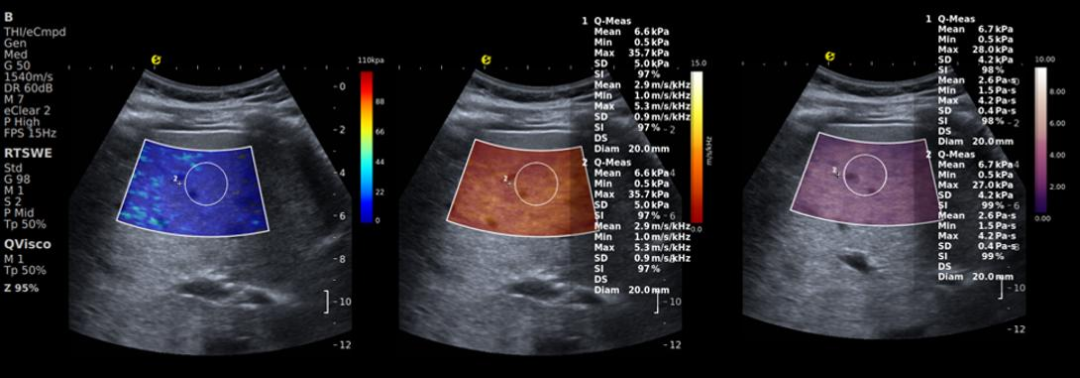

人体肝脏部位的E成像(RTSWE,左)

剪切波频散成像(SWD,中) 黏弹性成像(Viscoelastic,右)

E成像-RTSWE®

通过精准量化肝脏硬度,为肝纤维化分期提供客观的kPa值依据(参考Baveno VII共识对肝脏硬度检测的相关标准),其鉴别F2期及以上纤维化的AUROC值达0.87,显著优于传统血清学指标(如FIB-4、APRI),相关数据来自多中心临床验证研究。

黏弹性定量成像-QVisco™

可精准揭示肝脏组织微观病理改变,清晰呈现肝脏从“可逆功能异常”到“不可逆结构改变”的整个病理过程。该参数能够评估细胞水肿、炎症浸润及脂质堆积等细微变化,有效弥补了传统弹性技术对微观病变与炎症活动识别能力的不足,为肝脏病理分层提供了新的影像维度,已被多项临床研究证实其应用价值。